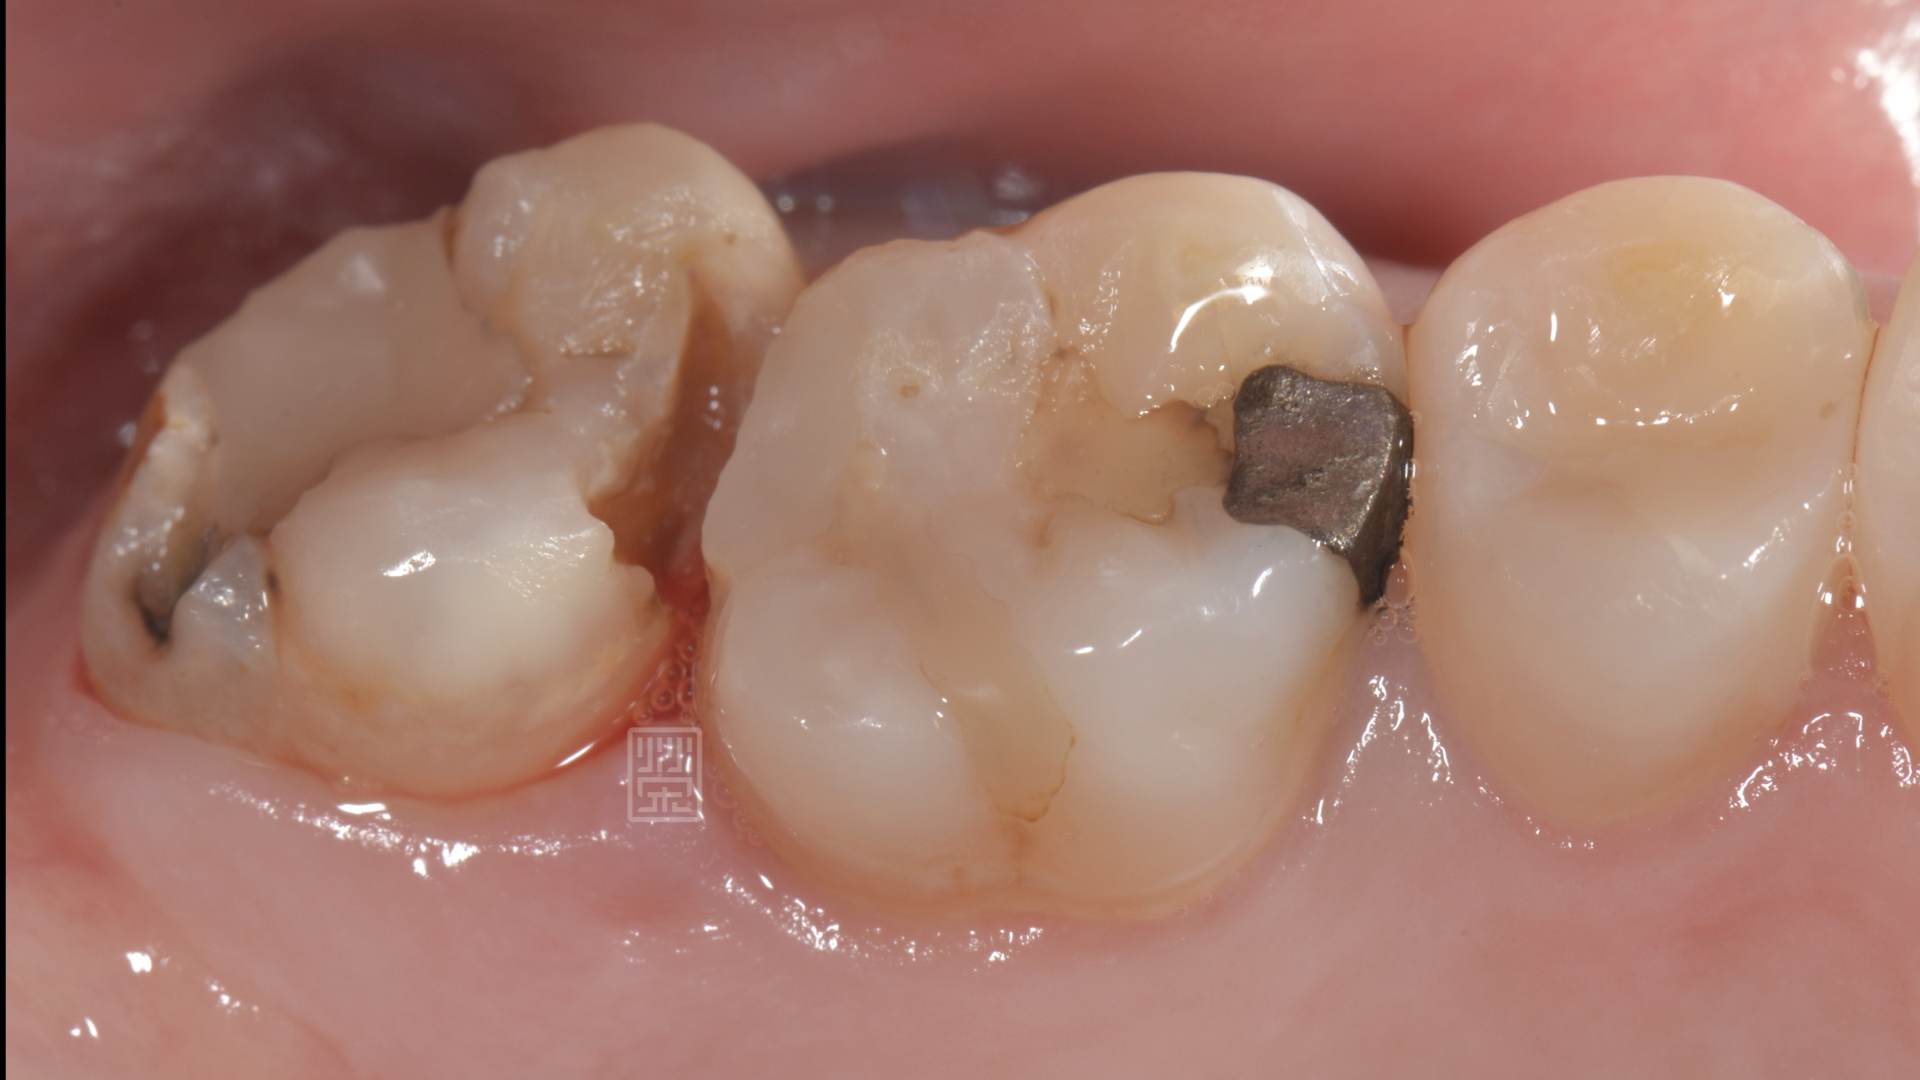

陳小姐某天吃東西,突然發現好像咬到硬硬的,但仔細一看,似乎不是食物,而是自己的牙齒!!!而且牙齒就空了一個洞,緊張之餘,馬上安排門診檢查。

經由診斷後,應該是蛀牙造成牙齒損傷,咬到硬物,牙齒斷裂,幸運的是,牙齒神經依然健康,只是牙齒齒質受損嚴重,

牙齒破裂

頰側大蛀牙